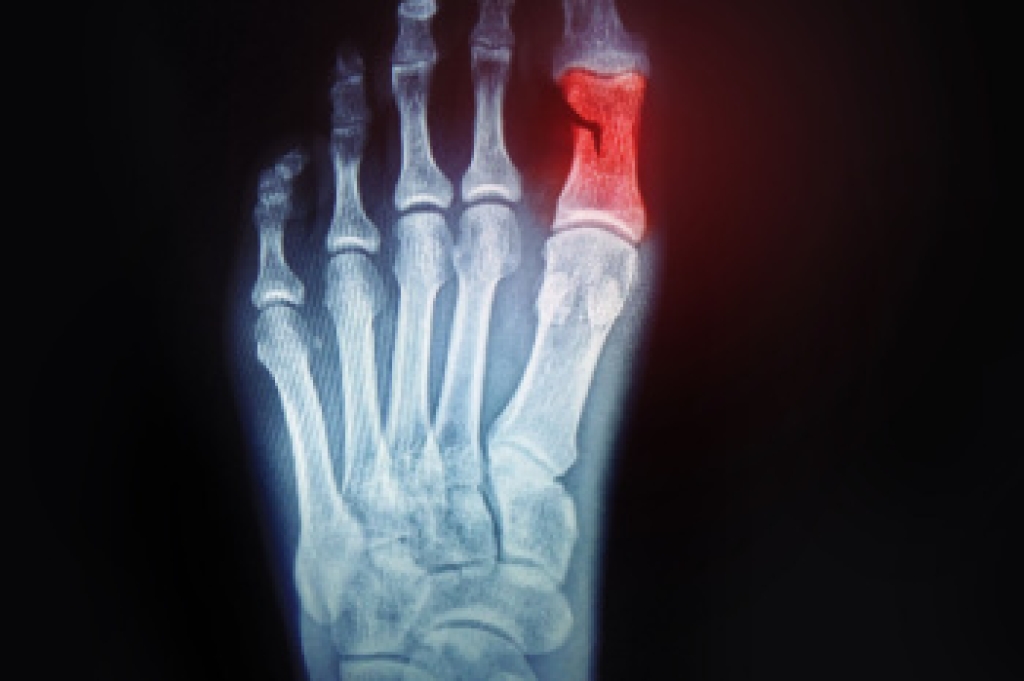

Ingrown toenails occur when a toenail grows sideways into the bed of the nail, causing pain, swelling, and possibly infection.